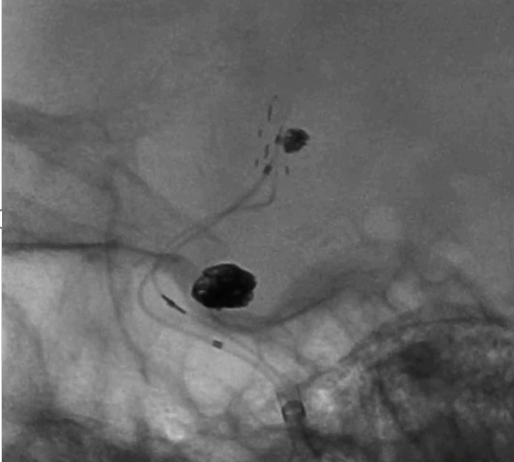

璞慧 0.017微导管塑形

Asahi 0.014微导丝塑形后辅助Echelon 10微导管进入A2远端备支架释放。

Asahi 0.014微导丝导引璞慧 0.017微导管进入动脉瘤内。

通过璞慧0.017微导管填入Target 1.5/2弹簧圈部分成篮,后释放Atlas 3.0/15支架覆盖瘤颈处,继续填入弹簧圈时微导管脱出,尝试用弹簧圈将微导管引导超选瘤腔失败。

撤出弹簧圈,Asahi 0.014微导丝引导璞慧 0.017微导管穿支架网孔进入动脉瘤内。